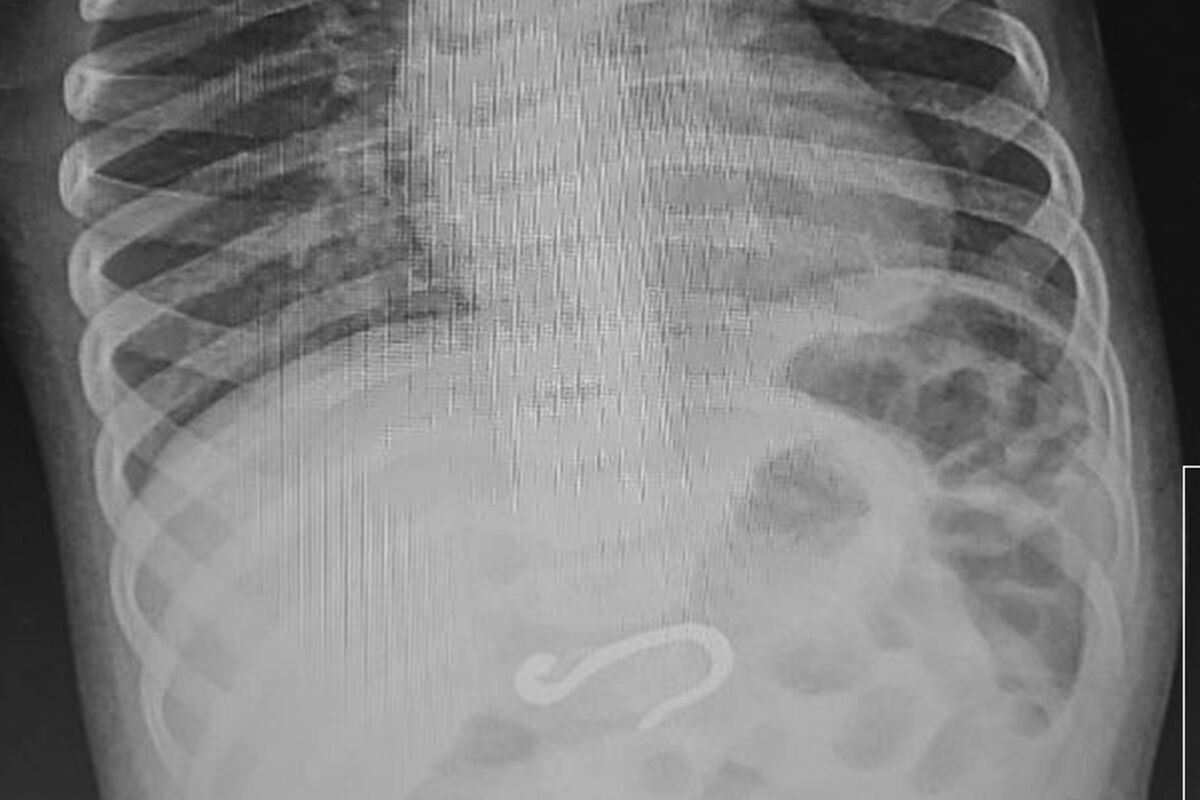

Восьмимесячный мальчик поступил на днях в экстренный приемный покой ЧОДКБ с подозрением на проглоченный колпачок от ручки. Однако рентген показал, что в его желудке находится металлический крюк внушительных размеров, который уже частично погрузился в двенадцатиперстную кишку.

Сначала врачи решили переместить инородное тело из кишки в более просторное место желудка, а затем подцепить и аккуратно извлечь наружу. Операция длилась час и прошла успешно. Тогда же выяснилось, что крюк не вызвал внутренних повреждений, и маленький пациент вскоре отправился домой.